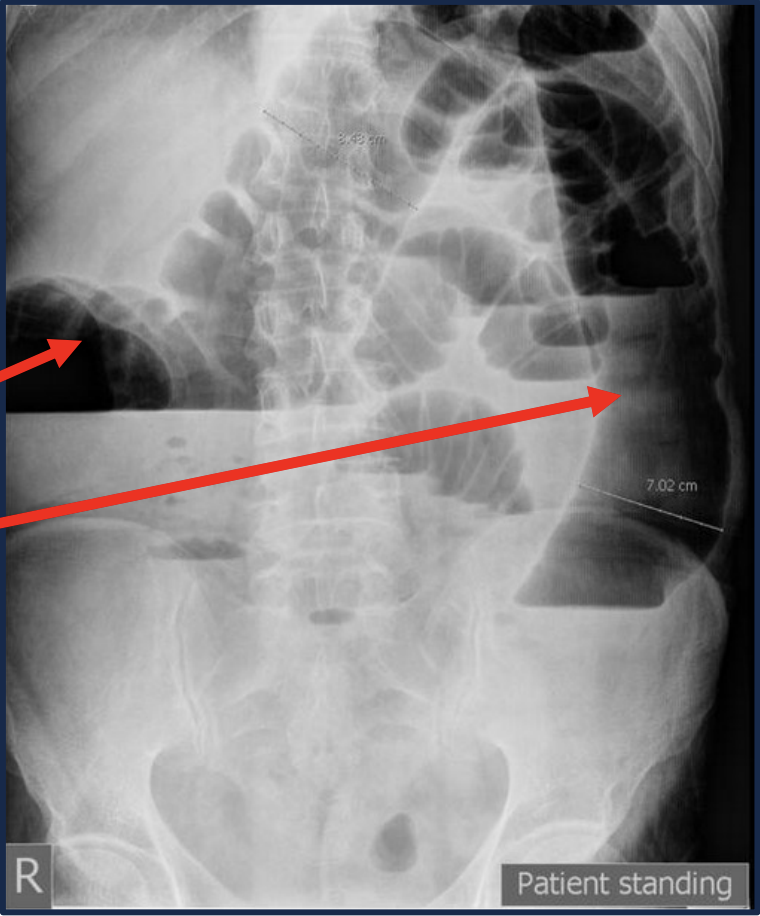

The following abdominal x-ray shows _

The following abdominal x-ray shows air-fluid levels suggesting bowel obstruction

* The obstruction point appears to be in the descending colon, possibly sigmoid colon